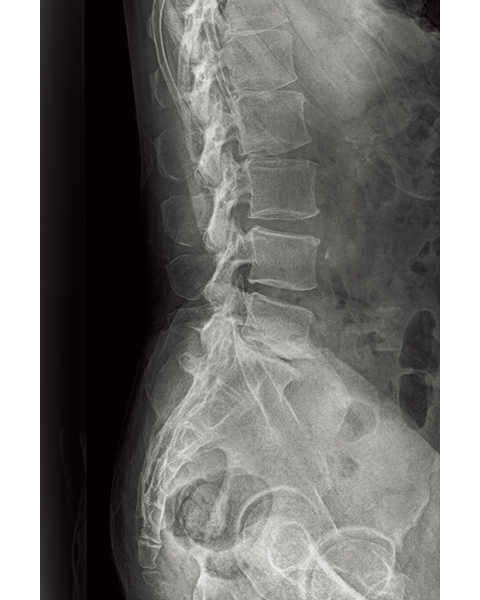

Dynamic Visualization II

Optimizes image quality using latest Exposure Data Recognizer

Advanced recognition algorithms using automatic  calculations of estimated 3D image data, identify the body part required and adjusts contrast, density and enhancement for optimised image display. (Option)

Comparison of Dynamic Visualization II vs. conventional processing images (Hip Joint)